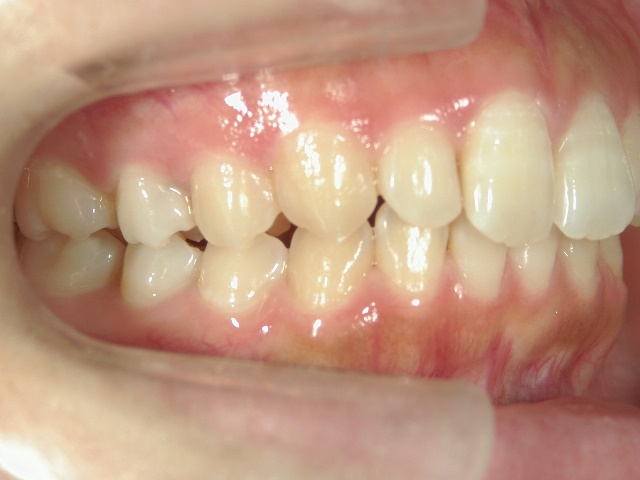

矯正歯科 治療前 右